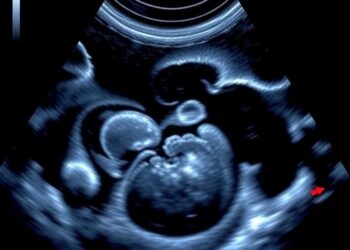

Real-Time Ultrasound Confirms Neonatal Tube Placement Accurately

In a groundbreaking revelation poised to reshape neonatal intensive care, recent research has brought to light the unparalleled diagnostic precision ...